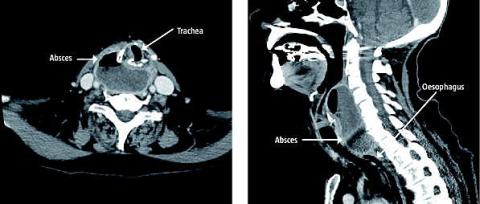

En 83-årig kvinde blev indlagt til hoftealloplastik. På grund af problemer med spinalanalgesien skiftede man til generel anæstesi. Der blev gjort fem forsøg inden succesfuld intubation. To dage efter indgrebet klagede patienten over svag stemme, synkebesvær og smerter til højre øre. På sjettedagen postoperativt blev der foretaget øre-næse-hals-tilsyn, hvor man fandt hævelse af pharynx' bagvæg. På grund af patientens penicillinallergi indledte man en erythromycinbehandling. På niendedagen udviklede patienten synkestop, og hun blev derfor overflyttet til øre-næse-hals-afdelingen. Her foretog man en akut computertomografi af halsen, som viste en 6 ×7× 3 cm stor absces mellem larynx og columna cervicalis. Den afklemte fuldstændig oesophagus. Man udtømte samme dag 100 ml pus. Postoperativt blev patienten behandlet med cefuroxim, metronidazol samt solumedrol intravenøst. Dyrkning viste efterfølgende nonhæmolytiske streptokokker.

Efter en vanskelig intubation må man altid have in mente, at der kan opstå komplikationer såsom hæmatom, absces og perforation/fistel. Såfremt patienten efterfølgende udvikler halssmerter, smerter til øret, synkebesvær, globulusfornemmelse, hæshed eller stridor, bør overvejes akut billeddiagnostik og øre-næse-hals-tilsyn.